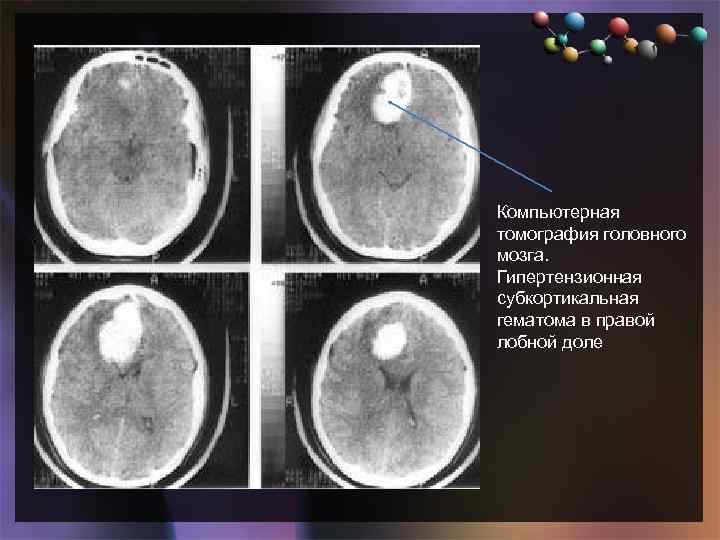

• Подзаголовок слайда Компьютерная томография головного мозга. Гипертензионная субкортикальная гематома в правой лобной доле

• Подзаголовок слайда Компьютерная томография головного мозга. Гипертензионная субкортикальная гематома в правой лобной доле

• Подзаголовок слайда Компьютерная томография головного мозга того же больного через 4 дня после операции — удаления внутримозговой гематомы правой лобной доли

• Подзаголовок слайда Компьютерная томография головного мозга того же больного через 4 дня после операции — удаления внутримозговой гематомы правой лобной доли